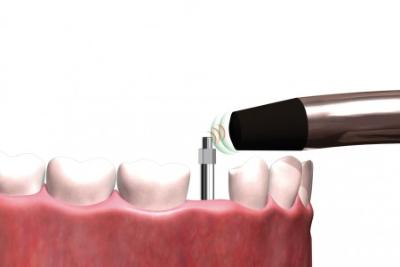

Osstell

Osstell è un valido ausilio per determinare in maniera oggettiva e non invasiva la stabilità dell'impianto e valutare la progressione dell'osteointegrazione, senza compromettere il processo di guarigione.